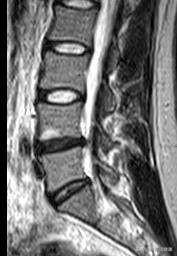

腰椎椎間板ヘルニアには間欠性跛行という症状がありますが、MRIを撮るとこのような腰部脊柱管狭窄症の症状が見つかることがありますが、腰部脊柱管狭窄症による間欠性跛行の多くは両側性で左右対称であり、片側性の痛みではないため、やみくもに腰部脊柱管狭窄症と診断することはできません!

これを腰部脊柱管狭窄症とみなし、手術が必要だと言う人もいるかもしれませんが、実はそうではありません。 片側の坐骨神経痛は、特にこの問題が非常に起こりやすいL4-5腰椎椎間板ヘルニアの患者に非常に多く、もちろん脊柱管狭窄症や足の長短(骨盤の傾き)を同時に伴うこともあります。

この問題が発生したとき、私たちは急いでCTやMRIの結果に目を固定するべきではありません、ヘルニア物質は、大規模なレポートでは腰部脊柱管狭窄症を持っているかもしれませんが、それは脊柱管狭窄症が確実に症状を引き起こすことを意味するものではありません、ヘルニア髄核は脊柱管の容積を占有し、その結果、脊柱管の直径が減少し、ヘルニア者は症状がないかもしれないという意味で変性である。

実際、間欠性跛行は腰部脊柱管狭窄症の主な特徴であるが、それ以外の腰椎突出部は二次性脊柱管狭窄症になりやすく、特に円錐骨外側後縁や関節隆起部に骨軟化症がある重症患者では、二次性腰部脊柱管狭窄症になりやすいため、間欠性跛行という症状を発症する。したがって、腰椎滑膜症患者は、間欠性跛行発症後に脊柱管狭窄症の可能性も考慮する必要がある。

すでに述べたように、間欠性跛行は腰部脊柱管狭窄症の一般的な症状であり、このため脊柱管狭窄症に注意することが重要である。腰部脊柱管狭窄症は、脊柱管、神経根管、椎間孔などが様々な原因で狭窄し、脊髄、馬尾、脊髄神経根などが対応する部位で圧迫された状態です。臨床症状としては、腰痛、馬尾または腰部神経根の圧迫、神経原性間欠性跛行などの症状もみられます。また、腰部脊柱管狭窄症は、中等度から重度の腰椎椎間板ヘルニアに続発する可能性が高い。

100メートル歩いて休憩を要し、また歩けるようになるのは、症状的には間質性跛行であり、通常、しゃがむか座って休むことを好む。最も一般的なのは脊柱管狭窄症で、骨性脊柱管狭窄症か椎間板ヘルニアに続発する脊柱管狭窄症である。歩行距離が100mしかなく、画像診断で裏付けられた場合は、手術を考慮すべきである。